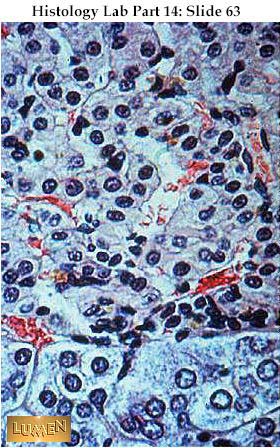

What two parts of the adrenal gland are shown on this slide?

zona reticularis and adrenal medulla